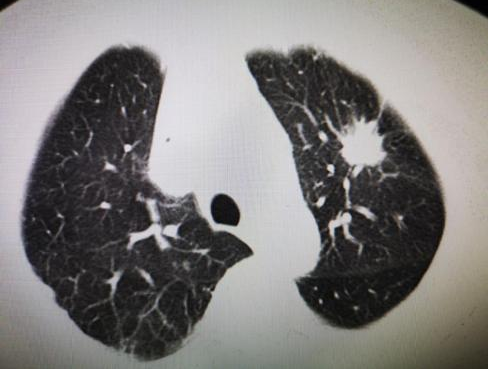

【医声守护·科普】第340期:关于肺结节那些事——重庆医药高专附一院胸心外科专家赵晓龙主任医师带您了...